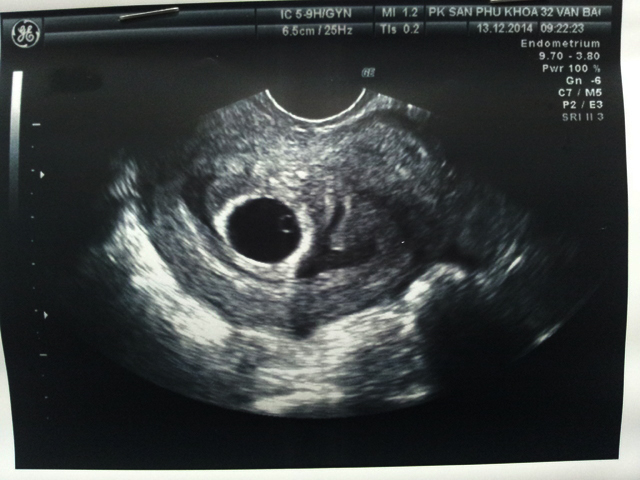

Việc siêu âm có túi thai nhưng chưa thấy phôi thai ở tuần thứ 5 là bình thường, bác sĩ sẽ khuyên mẹ nghỉ ngơi khoảng 1-2 tuần rồi kiểm tra tiếp hoặc ngay khi có những biểu hiện bất thường như ra huyết, đau bụng. Tùy từng kết quả siêu âm kiểm tra lại, nếu vẫn chưa có phôi thai, bác sĩ sẽ tìm nguyên nhân và cho mẹ giải pháp hợp lý nhất.

Việc siêu âm có túi thai nhưng chưa thấy phôi thai ở tuần thứ 5 là bình thường (Ảnh minh họa)